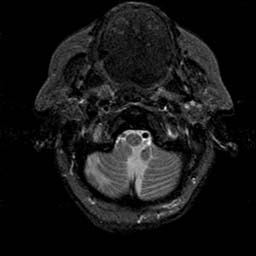

To demonstrate the effectiveness and efficiency of the proposed image fusion method , we conduct a set of comparative experiments on three image datasets. The first is composed by 8 pairs of multi-modal medical images and the second one contains 15 pairs of multi-focus gray or color natural images. These two datasets are often used in many related papers and some examples are shown in Figure 3(a) and Figure 3(b). The third one is a new multi-focus cervical cell image dataset collected by ourselves, which consists of 15 groups of color images and each group contains a series of multi-focus cervix cell images with size of or , etc. Some source examples are shown in Figure 3(c). Our source code implemented in C++ along with the new multi-focus cervical cell image dataset is available online.

We first evaluate the performance of the proposed method under varying total number of octaves and number of layers sampled per octave. The fused images of a pair of multi-modal medical images with different and are shown in Figure 4. In this example, on the one hand, when only 1 or 2 octaves are involved in constructing the DoG pyramid, the fused images fail to keep the integrity information of large size objects (e.g. eyeballs), while by increasing the value of , the integrity information of eyeballs is preserved. On the other hand, although not as significant as the increase of octave numbers , the fused image can contain more details by the increase of layer numbers . The corresponding objective quality metrics are shown in Figure 5. As shown in Figure 5(a), most of the metric values are improved as the number of octaves increases with the fixed layer numbers 3 in the global tendency and each of them tends to be stable when the number of octaves is 5. To get a relatively good quality from Figure 5(b), we can notice that some of the metric values can get a good performance when the number of layers is 3, such as the MI, SSIM, QI and VIF, though there are only a little change of all the metric values by increasing the number of layers with the fixed octave numbers 5. Because it will result in more computation burden with the increase of the value and , and for different kinds of source images, there are different performance with the diverse parameter settings. To get a trade-off between them in our experiments, we set for the multi-modal dataset, for the natural datasets and for the multi-focus cell dataset, respectively.

Figure 6 shows the fused images obtained by different methods with the multi-modal source images shown in Figure 3(a). As shown in these figures, the proposed method can produce images which preserve the complementary information of different source images well. Moreover, due to the scale-invariant structure saliency selection, our method can keep the integrity information of large size objects and the visual details simultaneously. Although the fused image generated by other methods can also capture the details to some extent, all of them fail to keep the integrity information of large size objects such as the eyeballs. Furthermore, from Figure 6(k)-6(t), the DTCWT, GFF, IM and NSCT methods may decrease the brightness and contrast while the proposed method can preserve these features and details without producing visible artifacts and brightness distortions.